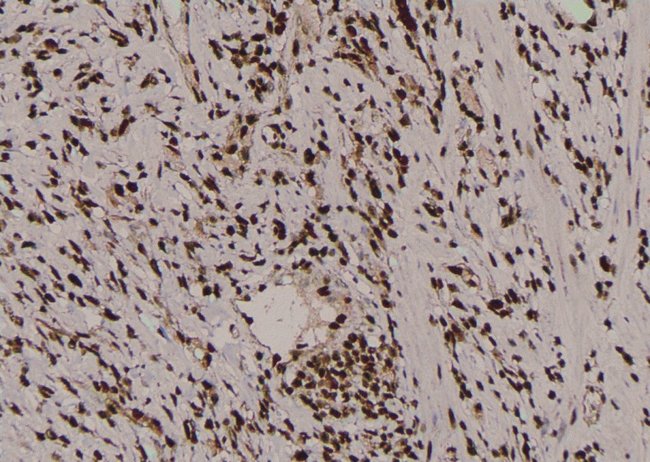

Invitrogen™ Phospho-PKC alpha (Tyr195) Polyclonal Antibody

Antibody detects endogenous levels of PKC alpha only when phosphorylated at Tyr195.

| Immunohistochemistry (Paraffin), Western Blot, Immunocytochemistry | |

| A synthesized peptide derived from human PRKCA(Accession P17252), corresponding to amino acid residues around phosphorylated Tyr195. | |

| Human, Mouse, Rat | |